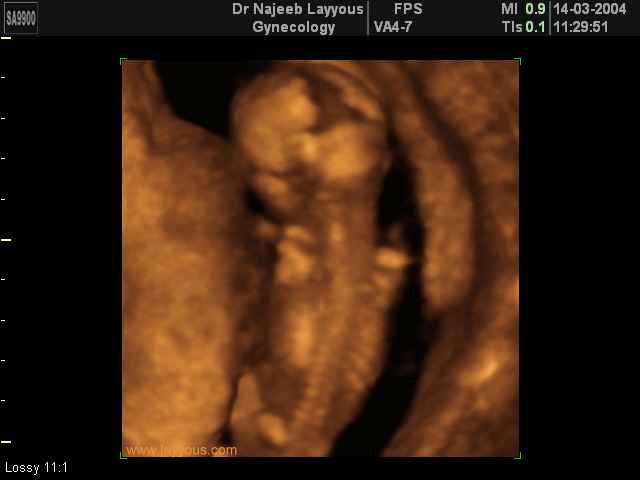

صور لأعضاء الجنين بجهاز الموجات فوق صوتية ثلاثي الأبعاد | الدكتور نجيب ليوس

صور لأعضاء الجنين بجهاز الموجات فوق صوتية ثلاثي الأبعاد